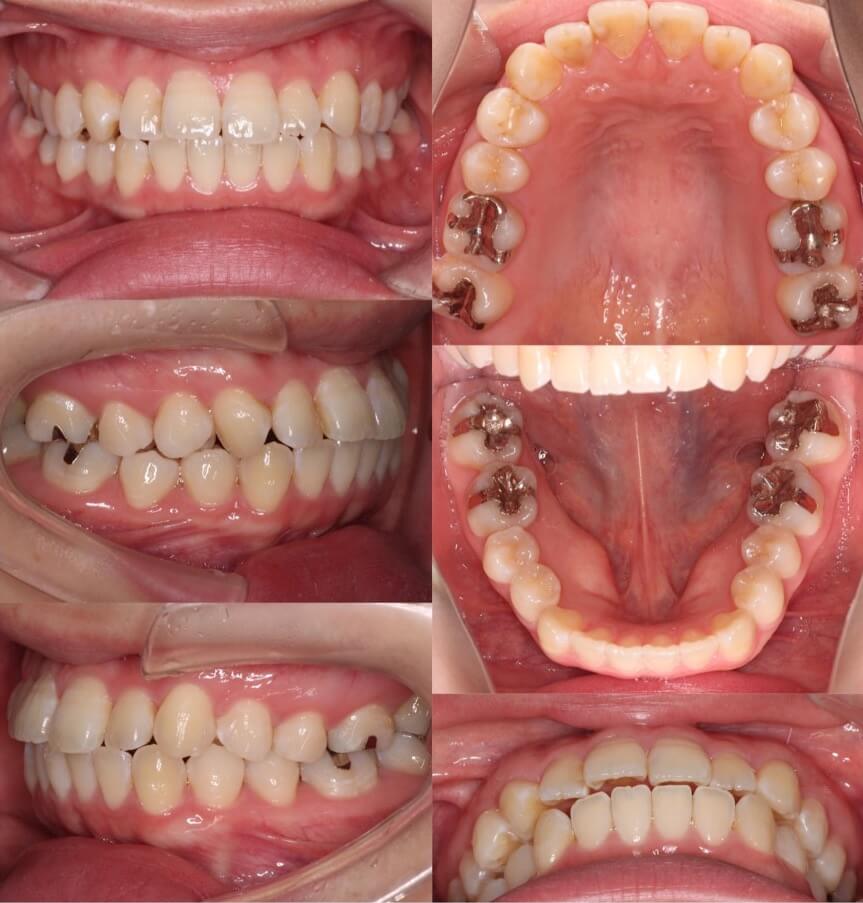

「開咬ならマウスピースも可能」

20代女性・マウスピース型装置・前歯傾斜型

マウスピース型矯正治療は前歯の歯根の後方移動が難しく、口ゴボ症例の適応症は少ないと言えます。その中で、開咬症例は数少ない適応症です。外開きになっている前歯を傾斜移動をコントロールしながら、後方移動させました。

<症例概要> 難易度:★★★★☆

主訴:口元の突出と前歯のかみ合わせ

年齢・性別:20代女性

住まい:千葉県八千代市

症状:開咬・上下顎前歯唇側傾斜・叢生

治療方針:抜歯空隙の閉鎖(中等度固定)

治療装置:マウスピース型矯正装置(アライナー装置)

抜歯:上下左右4番(計4本)

治療期間:2年1か月

アライナー枚数:29+27+20ステージ

リテーナー:上下クリアタイプ+フィックスタイプ

治療費用:990,000(税込)

代表的副作用:痛み・治療後の後戻り・歯根吸収・歯髄壊死・歯肉退縮